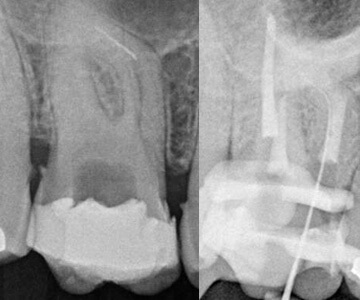

Oberer beschwerdefreier Schneidezahn mit sichtbar zu „kurzer“ Wurzelfüllung, die nicht an die Wurzelspitze heranreicht und sich sehr undicht darstellt. Der Zahn soll eine neue Krone bekommen (Bild links).

Im Zuge der Revision entfernter alter metallischer Wurzelkanalstift (Bild Mitte).

Zustand nach Wurzelkanalrevision, d. h. Desinfektion, erneute Wurzelfüllung und moderner Wurzelkanalstift aus Glasfaser (Bild rechts).